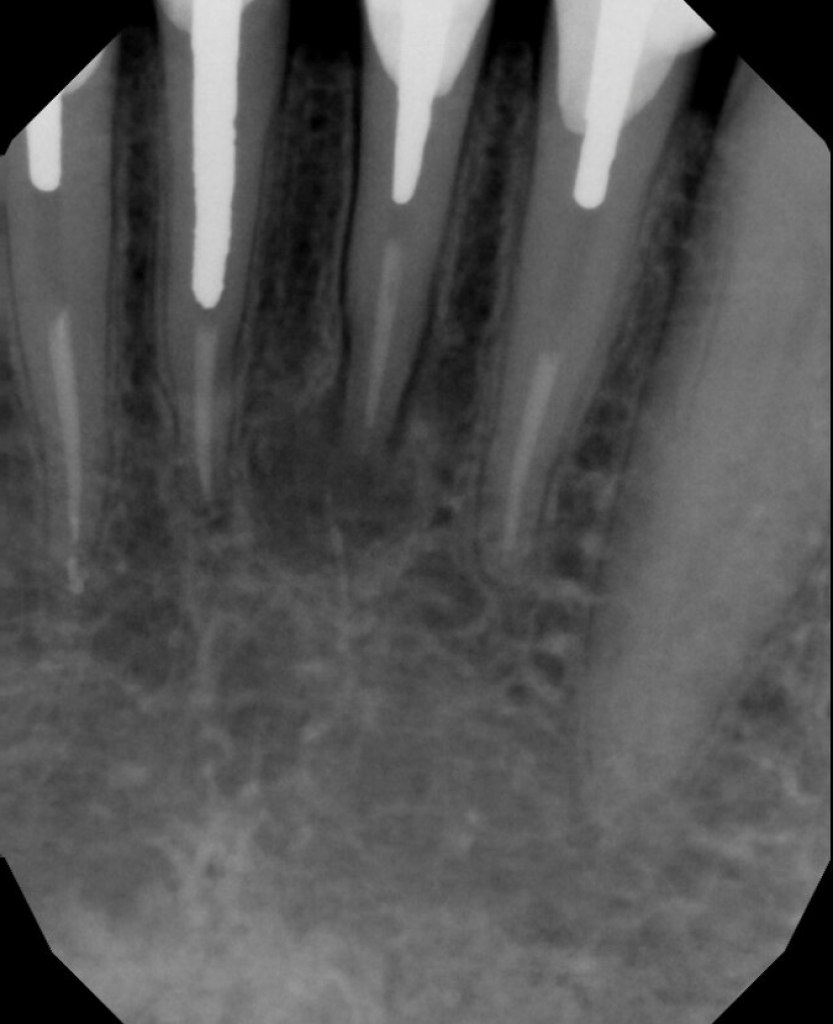

#31 NS-RCT